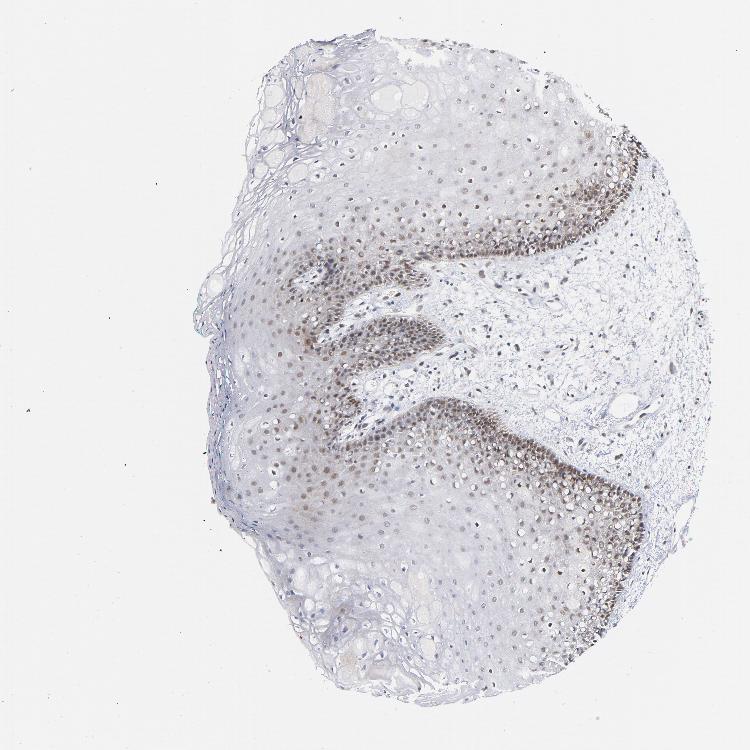

TISSUE PRIMARY DATA ORAL MUCOSA Show tissue menu

ORAL MUCOSA - Antibody stainingi

Antibody staining in the annotated cell types in the current human tissue is reported as not detected, low, medium, or high, based on conventional immunohistochemistry profiling in selected tissues. This score is based on the combination of the staining intensity and fraction of stained cells.

Each image is clickable and will lead to virtual microscopy that enables deeper exploration of all samples and also displays staining intensity scores, fraction scores and subcellular localization as well as patient and tissue information for each sample.

Antibody HPA028814Antibody CAB004322

Squamous epithelial cells MediumMedium